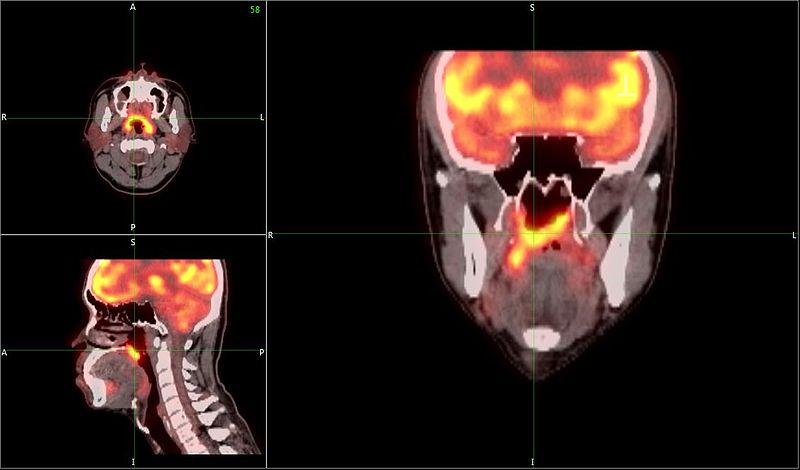

Το PET-CT SCAN είναι σημαντικό διαγνωστικό εργαλείο

Πρώιμη διάγνωση καρκίνου με PET-CT